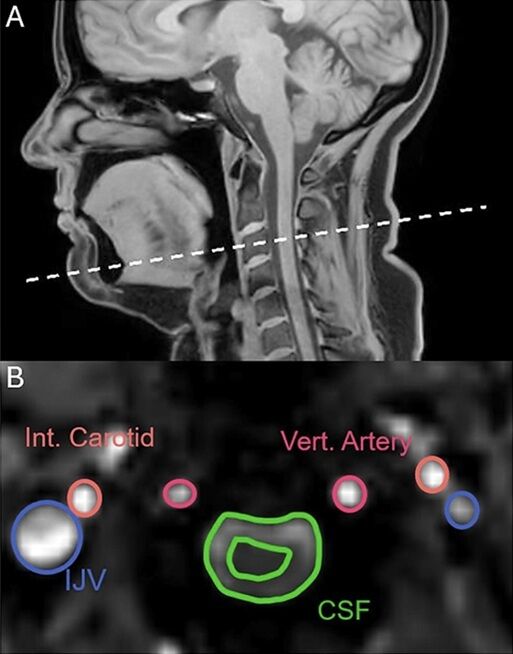

Автори роботи – команда з Університету Нового Південного Уельсу в Австралії – досліджували фізіологію позіхання за допомогою магнітно-резонансної томографії. У дослідженні взяли участь 22 здорові добровольці. Їм по черзі пропонували позіхати, глибоко вдихати, стримувати позіхання та дихати у звичному режимі. Наразі робота ще не пройшла рецензування, але вже опублікована на платформі bioRxiv.

Оскільки позіхання та глибокий вдих мають схожі механізми, дослідники припускали, що й результати МРТ будуть майже ідентичними. Проте скани показали принципову різницю. На відміну від глибокого дихання, позіхання змушувало спинномозкову рідину рухатися від мозку, а не до нього. Це стало ключовим і несподіваним відкриттям.

Окрім руху спинномозкової рідини, аналіз показав ще одну важливу деталь. І глибоке дихання, і позіхання посилюють відтік крові від мозку. Це, своєю чергою, створює простір для надходження нової, насиченої киснем крові. На ранніх етапах позіхання кровотік у сонній артерії збільшується приблизно на третину.